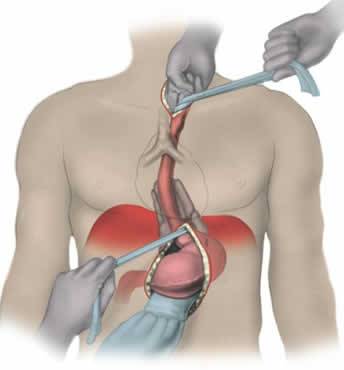

Esophageal Cancer

The esophagus is a long, muscular tube that runs from the throat to the stomach. The esophagus is made up of several layers of muscle t...